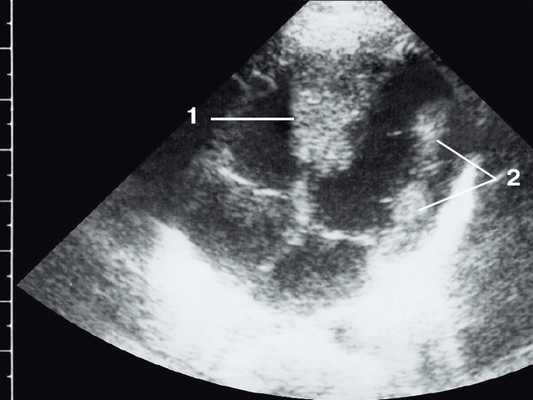

Рис. 2. Эхокардиограмма матери этого же ребенка. В межжелудочковой перегородке несколько эхоплотных образований (стрелки).

Рабдомиома сердца эхографически выглядят как достаточно четко очерченные образования. Чаще всего располагаются в миокарде левого желудочка, реже - в правом, еще реже - в предсердиях, кавоатриальных и атриовентрикулярных соединениях, эпикарде. Метастазирование не типично [8]. Наличие двух и более рабдомиом четко коррелирует с туберозным склерозом, одиночные рабдомиомы сердца такой связи, как правило, не имеют. По нашему опыту (18 пациентов), чем меньше объем новообразования, тем выше акустическая плотность, приближающаяся к эталонной эхоплотности (эндо-, эпи- и перикард). Эхоплотность больших рабдомиом практически не отличается от эхоплотности миокарда. В толще новообразования выявляются мелкие эхонегативные очажки (области некрозов) и эхопозитивные очажки (отложения кальция) (рис. 3).